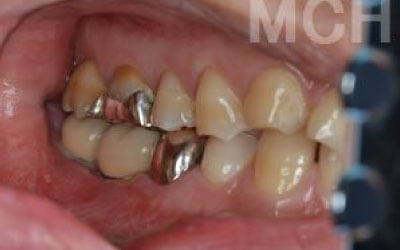

最も大きな違いは、前後の歯の寿命に影響を与えることです。

ブリッジでは、抜けた歯の前後の歯を大きな虫歯と同じくらいまで削らなければならず、

また、抜けた歯の代わりに前後の歯がその力を支えるため、常に1.5倍の負荷がかかります。

1)ブリッジ

2)歯を大きく削る+支えの歯に1.5倍の力がかかる

3)前後の歯の寿命が著しく減る

ブリッジの支えの歯は、データでは10年以内に68%が抜歯になります。